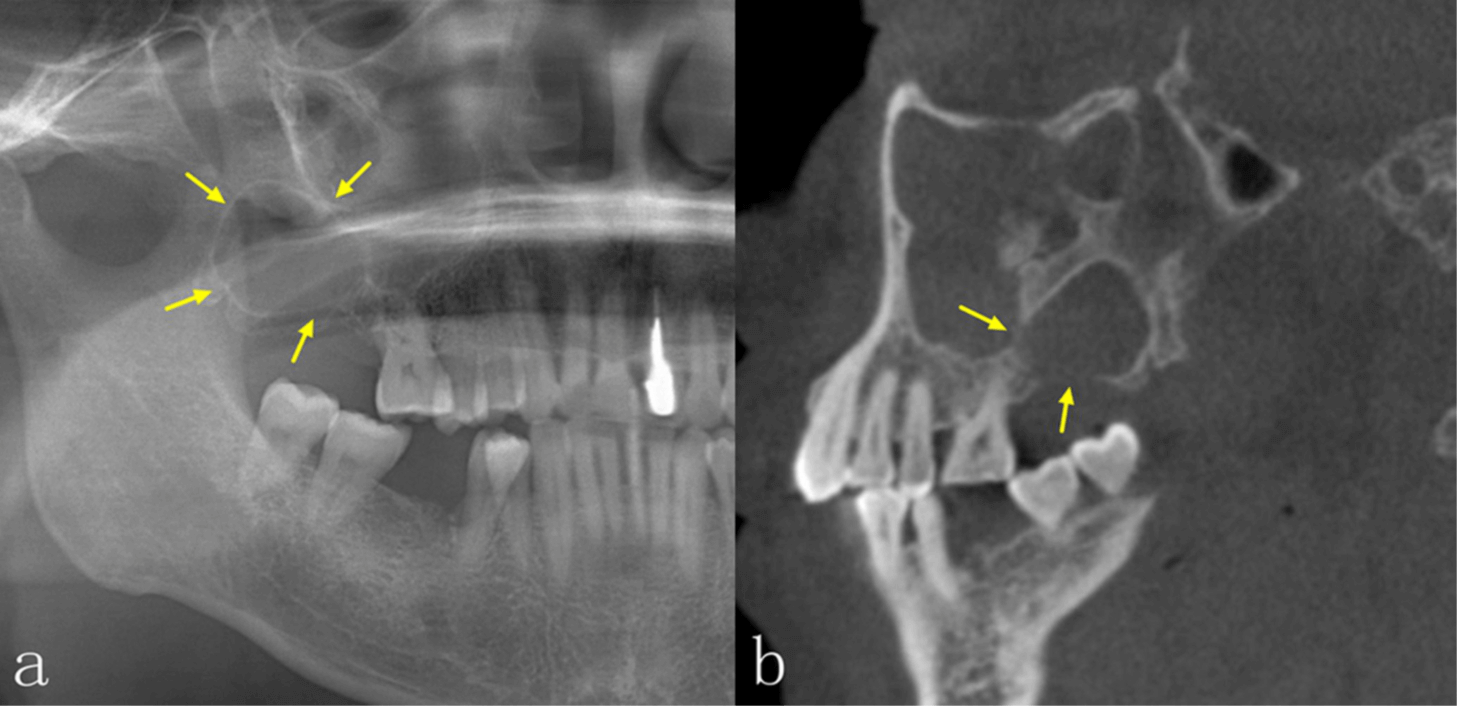

No obstante, la TCCB también tiene sus desventajas. Por ejemplo, la TCCB es propensa a diversos artefactos, especialmente artefactos metálicos y de movimiento, que pueden tener un efecto perjudicial sobre la calidad de la imagen. En comparación con la tomografía computarizada espiral (tomografía medica), su resolución de contraste es menor y los tejidos blandos se visualizan con menor calidad. La dosis de radiación y el coste son también factores importantes que deben tenerse en cuenta a la hora de tomar decisiones clínicas. La dosis depende principalmente del tipo de equipo y de los ajustes de exposición, incluyendo el campo de visión, el tiempo de exposición, la corriente del tubo (mA) y la energía/potencial (kV).6 En comparación con la PAN, la dosis efectiva de radiación de la TCCB suele ser significativamente mayor, lo que debe tenerse en cuenta cuando se requiere la obtención de imágenes. Las diferencias significativas en el aspecto radiológico de las lesiones intraóseas entre la PAN y la TCCB se encuentran en la integridad de los bordes corticales, la expansión de los límites anatómicos circundantes, el adelgazamiento cortical, la destrucción cortical y la reabsorción radicular, especialmente en las regiones anteriores de ambos maxilares y en el maxilar superior. La TCCB también mejora la precisión diagnóstica, especialmente en las lesiones del maxilar superior.

La TCCB proporciona información más completa y detallada, lo que resulta útil para realizar el diagnóstico. Aunque la precisión diagnóstica estaba estrechamente relacionada con la experiencia de los médicos, la discrepancia entre los dos estudios se atribuye muy probablemente al mayor tamaño de la muestra de nuestro estudio. La TCCB fue precisa a la hora de mostrar las características de las lesiones, como la ubicación, la localización, la densidad interna, la expansión y su efecto sobre las estructuras circundantes, lo cual es de ayuda a los odontólogos a realizar un diagnóstico más preciso.